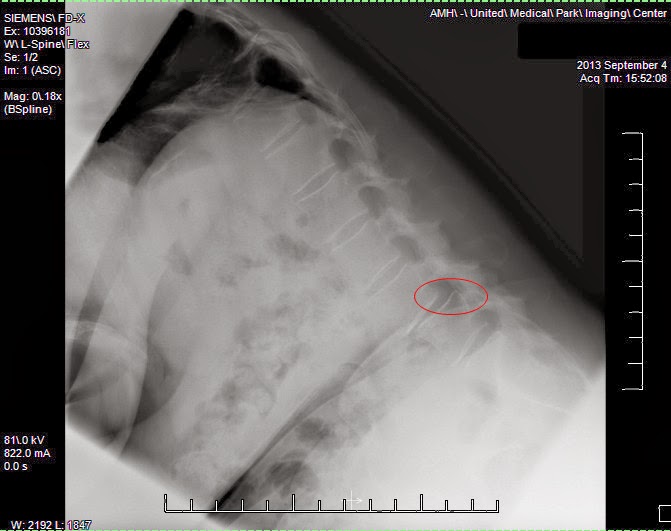

Known as "Spondy" for short - this is not a fun condition to have. What it means is that I have a slipping vertebrae in my spine. NOT a slipped disk (although I have that too). L4 sitting on L5 slips 10 mm forward (towards my stomach) when I bend forward. When I don't bend it's slipped by 3 mm. Needless to say I now know why, when I bend forward or reach forward, it hurts like crazy.

Here's a photo of an X-Ray of me bending forward:

Here's the same photo showing how the vertebrae below this point are nicely lined up, then the slippage occurs: